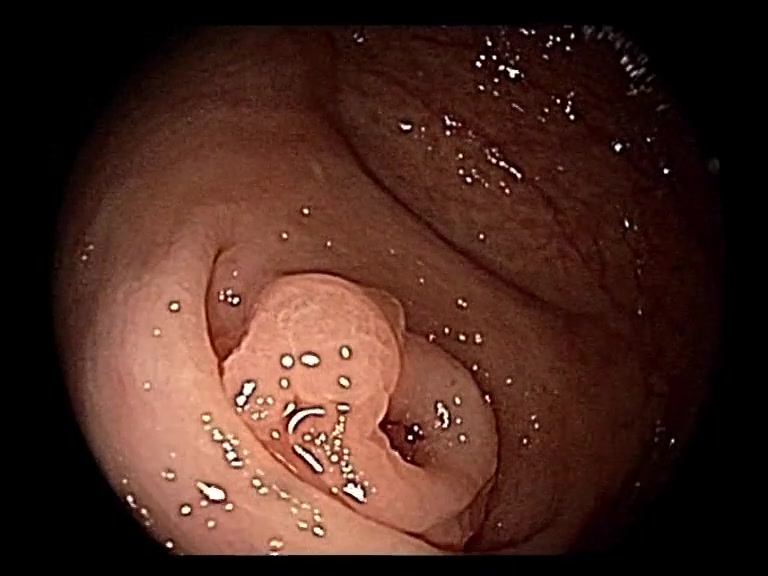

| Lesion | White Light Frame | NBI Frame | White Light Video | NBI Video | Camera Calibration |

| serrated_01 |  |

|

WL.mp4 | NBI.mp4 | cam.xml |